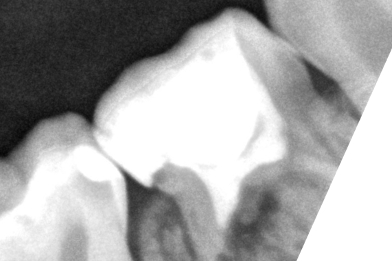

Для чего нужен КТ снимок? Не всегда можно увидеть кариес невооружённым взглядом. Данный

Бояринов Сергей Эдуардович

случай показывает наличие скрытого кариеса, который образовался на контактной поверхности

4.5 зуба. Именно наличие такого кариеса можно обнаружить при тщательной диагностике с

применением КТ снимка. -

Выполнена изоляция рабочего поля. Под инфильтрационной анестезией раствором Артикаина 1:100000 1,7 мл. Препарирование кариозной полости зуба. Пломба Ceram•X™ светового отверждения. Анатомическая форма зуба и целостность контактного пункта восстановлены

Бояринов Сергей Эдуардович -